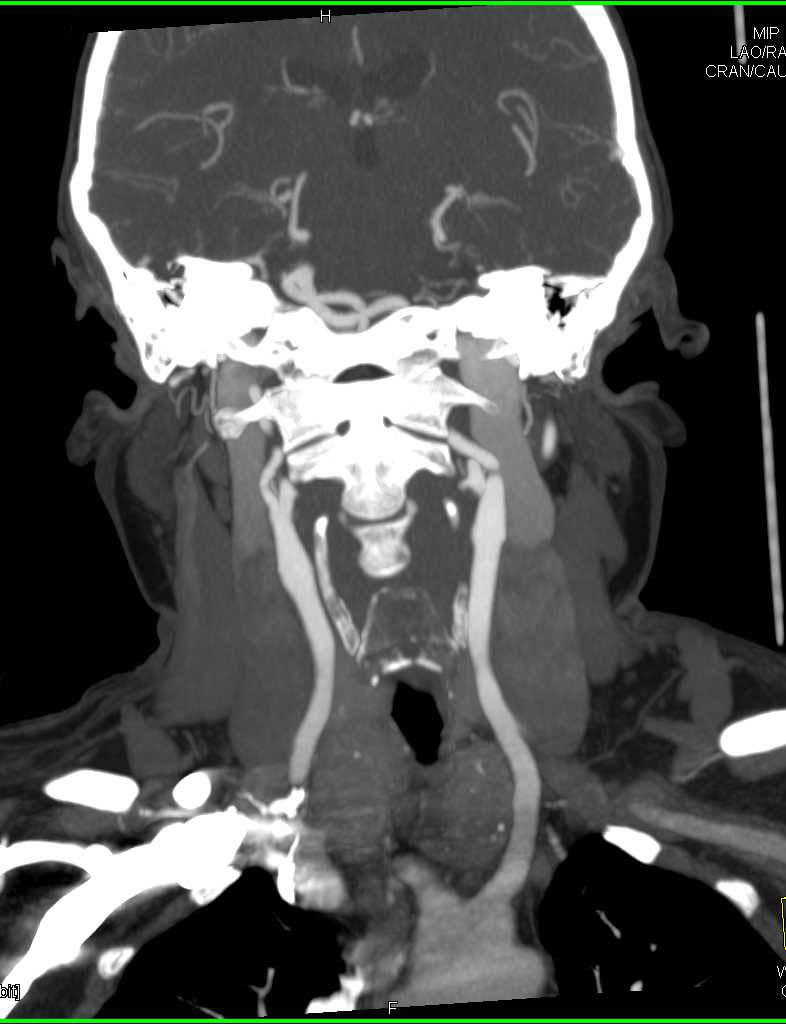

von Hippel Lindau with Right Renal Cell Carcinoma, and Hemangioblastomas to the Spinal Cord